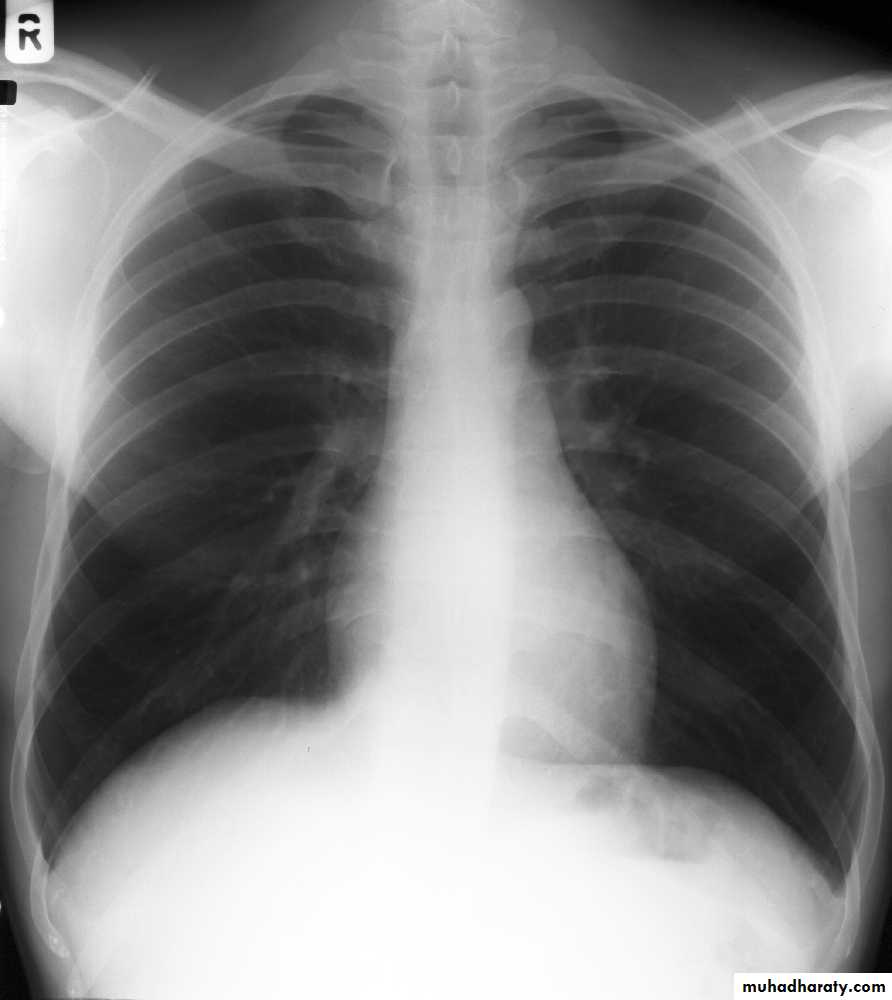

5)Full inspiration

The diaphragm should be below theanterior end of 6th rib & posterior end of 10th rib .

In expiratory film there is cardiac shadow enlargement , & vascular crowdening

Poor visualization of bases of the lungs1

Inspiration/Expiration